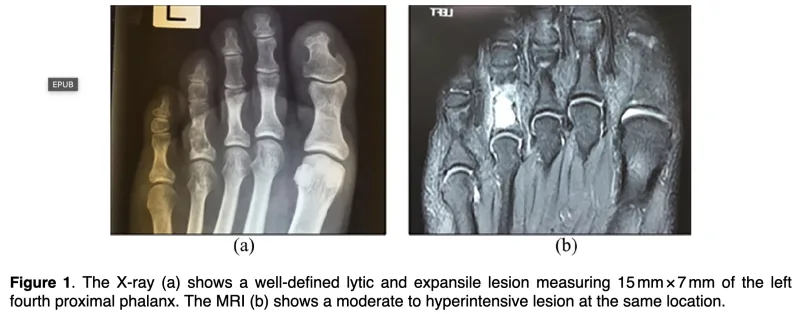

X線写真では, 腫瘍による骨破壊によって骨の中が透けるように黒っぽく写っていて, 内部に斑状の白い石灰化陰影を認めます.

MRI T2強調画像では, 水分含量の多い軟骨基質を反映して腫瘍部が白く描出されています.

1人は, 中高年の第4足趾基節骨の骨腫瘍が疑われた患者さんで, X線写真の所見から内軟骨腫が疑われました.

お二人とも, 造影MRIを撮像して, 診断することにしました.

予想通りに, 内軟骨腫と血管(静脈)奇形と診断.

内軟骨腫の患者さんは, 今回骨折したこともあり, 手術を勧めました.